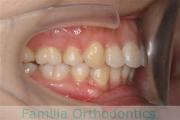

No.22V-146

- 主な症状:

- 叢生

- その他の症状:

- 上顎前突

- 年齢:

- 18歳

- 性別:

- 女性

- 抜歯部位

- 上:

- 44

- 下:

- 448

- 主な使用装置:

- FEA 022

- 治療にかかった費用:

- 85万円

口元をひっこめたいということで来院されました。過蓋咬合(深いかみ合わせ)と叢生(でこぼこ、ガタガタ)でしたので、上下左右から小臼歯を抜歯して、マルチブラケット法を行いました。3年弱、35回程度の通院が必要でした。

術前のかみ合わせが深いので、保定中に深くなってきやすいというリスクがありますので、リテーナーの使用状況が重要です。